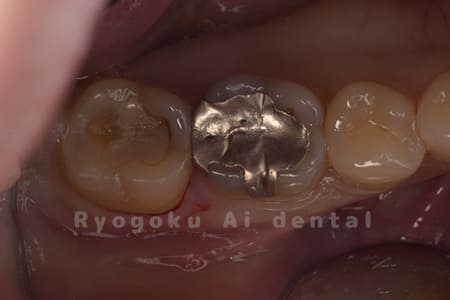

Case07

- セラミッククラウン

銀歯が浮いた感じがする、と相談された患者さんです。銀歯を外し、虫歯治療を行い、セラミックの被せ物で治療を行いました。